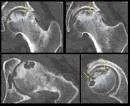

Case: septic arthritis, hip 14y old boy Presented with pain in R hip after history of a fall with abrasions few days before Had fever, limitation of R hip motion WBC: 13,000, ESR 23mm/1 hour Initial x-ray: not significant

Initial x-ray

X-ray 8 days later

X-ray taken on follow-up after surgical irrigation and debridement – too late!